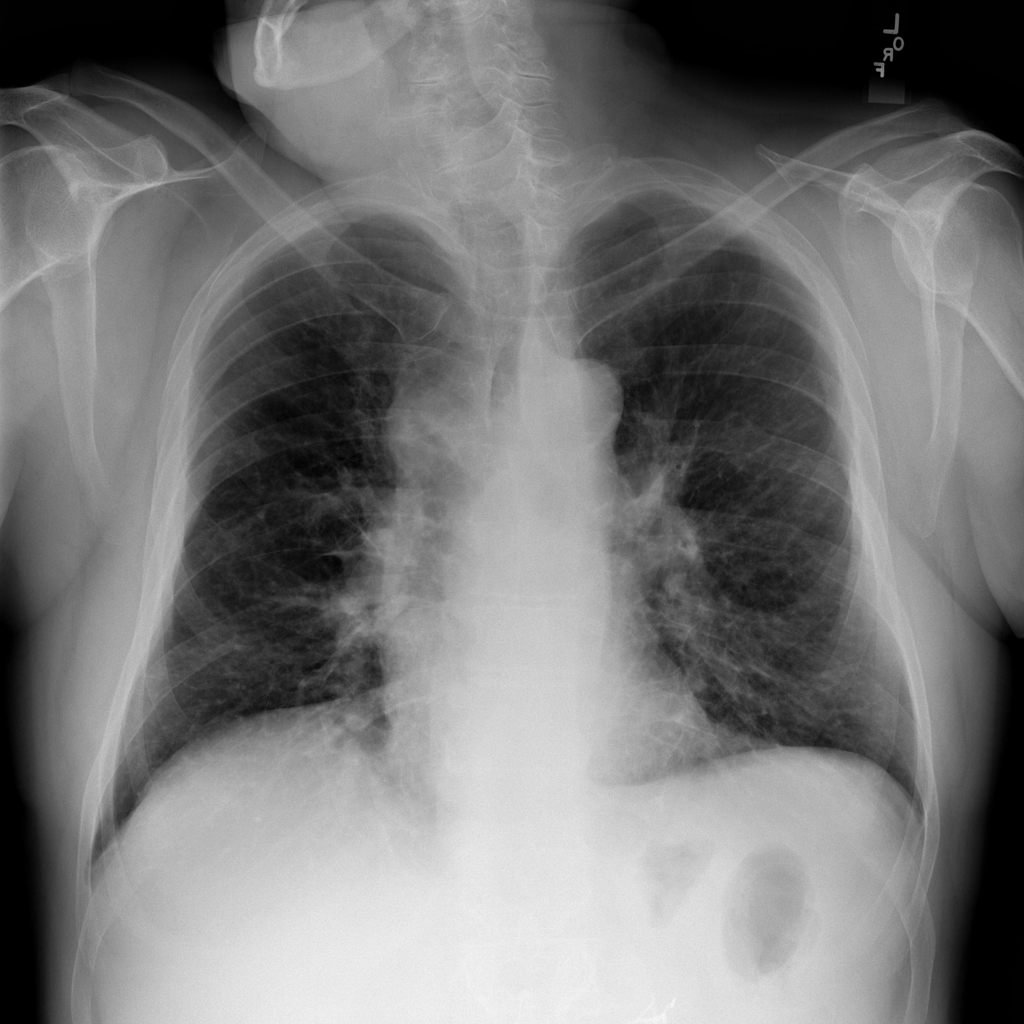

Mass

A mass is a larger focal opacity or lesion seen on the image. It is a descriptive finding that can have several causes and usually needs more imaging or clinical context to characterize.

PAT-C0E5 · IMG-001Mass

PAT-C0E5 · IMG-001

PA